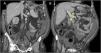

Al ingreso se mantuvo su tratamiento de base y se inició tratamiento depletivo (80mg/día de furosemida) y se colocó una sonda nasogástrica por vómitos de repetición. El paciente presentó una evolución tórpida inicial con diuresis escasa (1.000ml/24h), sin pérdida ponderal y empeoramiento clínico. A las 72 horas del ingreso, el paciente persistía con clínica sugestiva de suboclusión intestinal, por lo que se decidió solicitar una tomografía axial computarizada abdominal (fig. 1), dónde se observa un importante edema de partes blandas, de la pared intestinal, abundante ascitis e importante dilatación de la vena cava inferior, vena renal izquierda (1,59cm de diámetro, fig. 1A), venas hepáticas y vena porta (fig. 1B). Dados estos hallazgos, se intensificó el tratamiento diurético (250mg de furosemida/día) durante 7 días, con buena respuesta clínica (mejoría de su disnea y desaparición del cuadro suboclusivo), diurética (> 3.000ml/24h), de la función renal (fig. 2A) y de parámetros relacionados con la congestión (fig. 2B-D). A los 14 días se dio de alta al paciente en clase funcional II de la New York Heart Association, 15kg menos de peso y con mejoría muy llamativa del filtrado glomerular estimado (61ml/min/1,73m2).

Tomografía axial computarizada abdominal. A: Reconstrucción multiplanar en el plano coronal que demuestra la presencia de ascitis difusa (asteriscos blancos) y dilatación de la vena renal izquierda (flechas blancas). Se aprecia edema de la grasa del tejido celular subcutáneo (asteriscos naranjas) de forma bilateral en el área inguinal. B: Reconstrucción multiplanar coronal en un plano anterior a la imagen A que muestra importante ingurgitación vascular venosa de la porta extrahepática asociada (flechas amarillas).